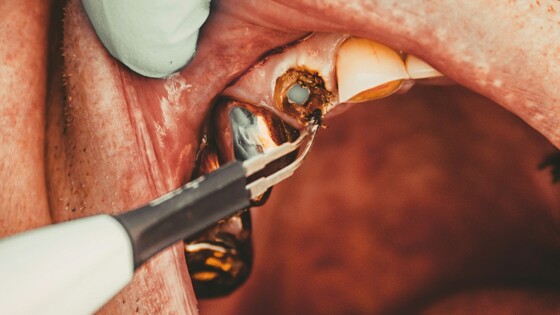

Кариес может перерасти в серьёзные проблемы, вплоть до значительного разрушения зубов. О возможных последствиях запущенных заболеваний челюсти рассказал «АиФ» врач-стоматолог Илья Антонов.

Разрушенный зуб — это источник инфекции, постоянно присутствующей в полости рта. Она может проникать в организм через пищу и слюну, разрушая окружающие ткани. Гной образует свищевой ход и вытекает из очага воспаления в полость рта. Это приводит к дальнейшему разрушению тканей.